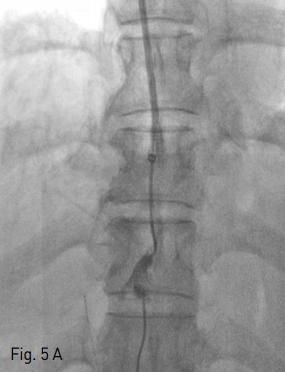

Fig 5A

A 5-Fr Davis catheter was advanced over the guidewire to the left portal vein, then a small amount of contrast material was injected through 5-Fr catheter to see the location of the left portal vein (A).

Fig 5B

After which, guidewire was introduced through the transjugular sheath and manipulated into the main portal vein and then superior mesenteric vein (B).